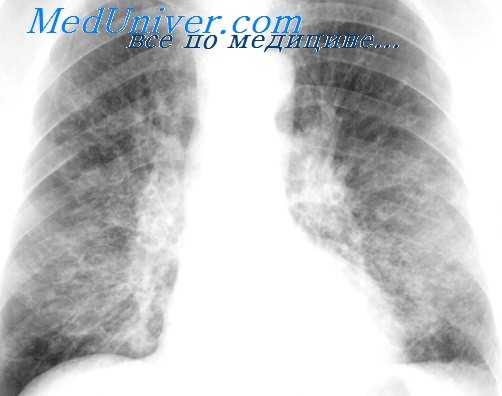

Рентгенологическая картина после торакопластики. На обзорных рентгенограммах и томограммах после экстраплевральной Т. определяется уменьшение объема оперированной половины грудной клетки и спадание соответствующего легкого. Степень уменьшения объема грудной клетки и легкого на оперированной стороне зависит от вида и объема Т. Рентгенологические изменения в легких наблюдаются при возникновении пневмонии, иногда осложняющей послеоперационное течение. В первые дни после операции могут возникать массивные ателектазы, в свою очередь осложняющиеся пневмониями. После обширной Т. может наблюдаться флотирование (маятникообразное смещение, синхронное с дыханием) средостения в области дефекта грудной стенки, исчезающее по мере регенерации костной ткани из оставшейся надкостницы ребер.

В отдаленные сроки после операции спавшееся легкое частично расправляется и вентиляция его улучшается за счет увеличения амплитуды дыхательных движений диафрагмы и ребер на стороне оперативного вмешательства, что отчетливо определяется на рентгенокимограмме (см. Рентгенокимография). В ряде случаев расправления легкого в отдаленные сроки не происходит вследствие развития в нем после операции пневмосклероза (см.), а иногда в последующем — бронхоэктазов (см.).

Определяемые после Т. тени регенерировавших ребер, особенно на фоне массивных плевральных шварт, затрудняют распознавание остаточных каверн и щелевидных остаточных полостей эмпием в случае неэффективной операции. Томография (см.) облегчает диагностику каверн в спавшемся легком, а фистулография (см.) и бронхография (см.) — выявление остаточных полостей.

У всех наблюдаемых нами больных был фиброзно-кавернозный туберкулез легких в фазе распада, инфильтрации и обсеменения. Размеры каверн колебались от 3 до 18 см. При наличии у большинства больных больших и гигантских каверн, как правило, отмечалось двухстороннее интенсивное очаговое обсеменение легких. Поэтому, имелась выраженная редукция функции внешнего дыхания, причем, преобладал ресгриктив-ный (ограничительный) компонент, о чем свидетельствовали снижение должных величин ЖЕЛ, МВЛ и коэффициента резерва у значительной части больных.